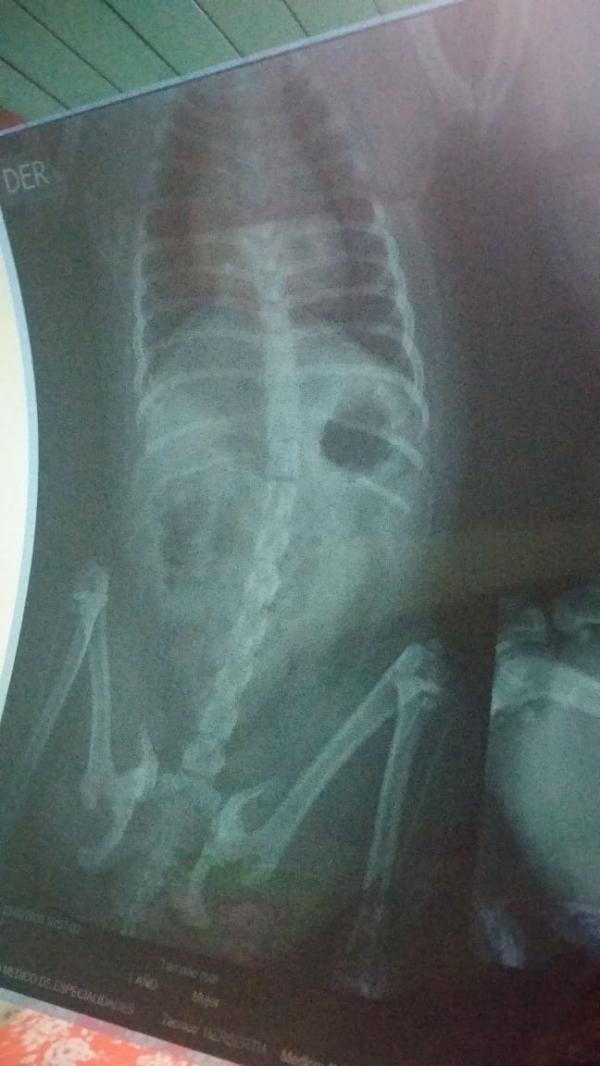

¿Qué hacer en caso de obstrucción intestinal en perros? Para detectar una obstrucción intestinal en perros el veterinario puede hacer una radiografía del abdomen. En ella se puede apreciar la distensión en los intestinos y una gran cantidad de gas. Aun así, jamás se debe medicar a un perro con síntomas sin diagnóstico veterinario ya que podría resultar contraproducente e incluso mortal.

Mi perrita de raza pug tiene más de 3 días sin hacer heces,comió algodón?? Le saque una radiografía